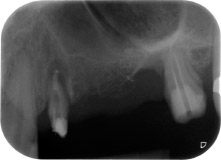

A 58-year-old female patient complained of pain and increased mobility of her bridge abutment tooth 24. Periodontal inflammation was present with pocket depths of 7 mm mesiobuccally and more than 12 mm distally, as well as third-degree furcation involvement. Moreover, the radiograph revealed an extensive periodontal lesion around the apical region of the (alio loco) endodontically pretreated tooth 24 (Fig. 1).

One year earlier, teeth 25 and 26 had been extracted due to trauma and for endo-perio reasons, prior to the placement of the bridge. A combined endo-perio lesion was diagnosed for tooth 24, of unclear aetiology. The patient wanted to keep her bridge abutment teeth 24 and 27 and would not accept a final, or even temporary, removable prosthesis. Therefore, it was agreed to make all efforts to retain both teeth, in spite of their poor prognosis as based on radiological and clinical findings.